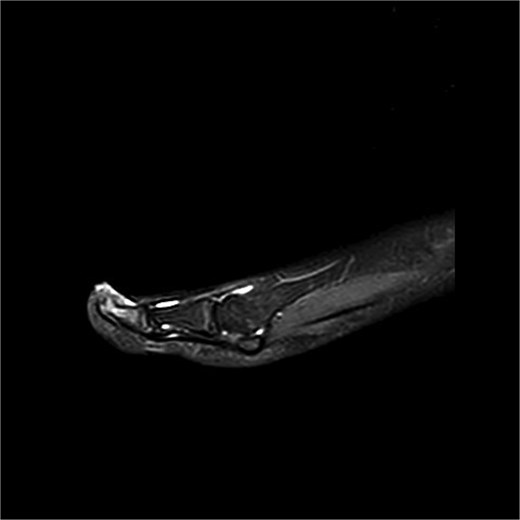

Case 2

Preoperative MRI from case 2 demonstrating SE and associated bone marrow edema.